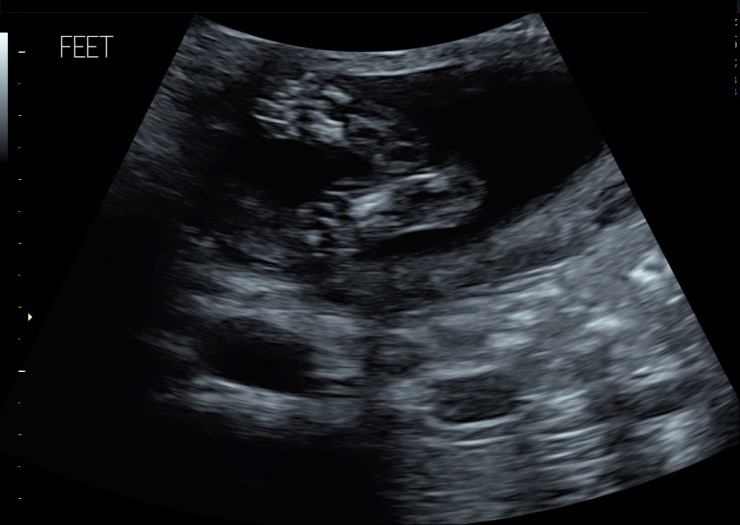

one awesome thing we got was quick little videos. one of them you can see her moving her mouth. omg. so fun to see her move her little mouth. kill me. she had her hands up by her face a lot in the scan and was super active and moving a ton, flipping side to side which is so cool to know in that little time how much she was moving and i can only imagine how much movement is going on during a normal day. she was moving like crazy, the MOST, i’ve ever felt after the scan, which i read was common. usually i have been able to only feel her when im holding still sitting or laying but i could feel her while i was walking around as well afterward! she probably was over all the poking and proding. i didnt realize how much they push on you in the scans.

LEFT HAND